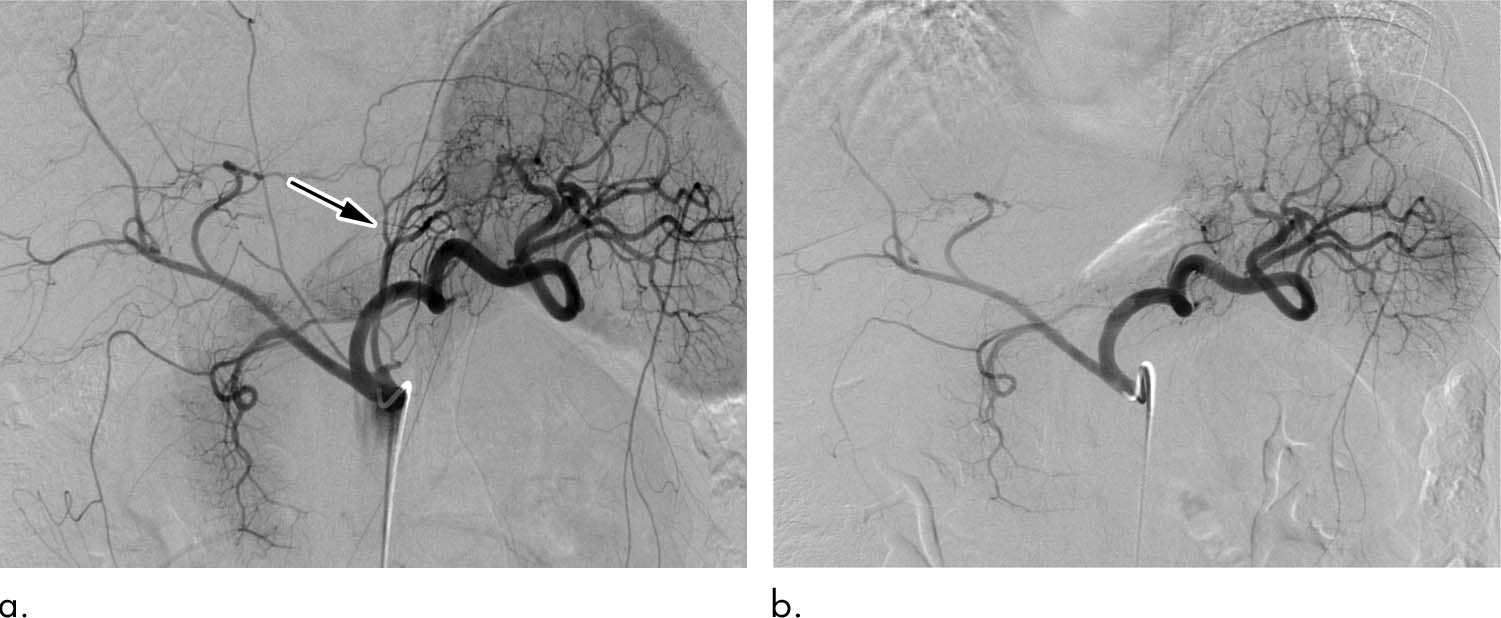

Эмболизация артерий предстательной железы при раке - фото презентация